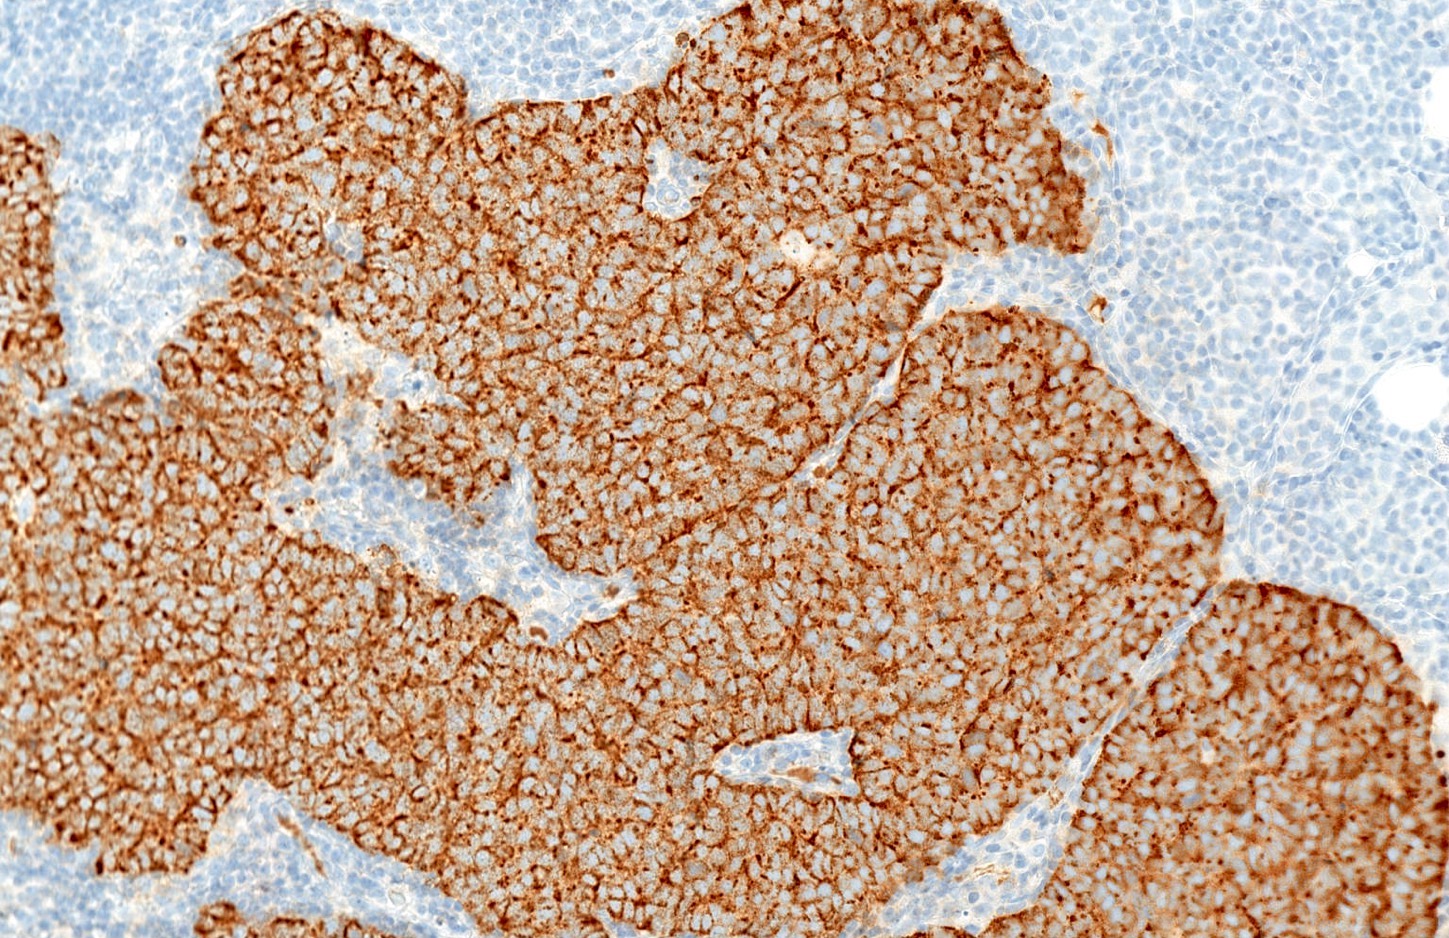

Microscopic (histologic) description

- Expansile, nodular or diffusely infiltrative tumor within the dermis, variably in subcutis

- Variable mixture of nodules, sheets, nests and trabeculae of neoplastic cells

- Intraepidermal tumor (or component) is occasionally present

- Generally, small round blue cell tumor with high N:C ratio, round / oval nuclei, finely dispersed chromatin (salt and pepper), indistinct nucleoli and scant cytoplasm

- Conspicuous mitoses and apoptotic bodies

- Variable nuclear molding and crush artifact

- Majority of cases display pure neuroendocrine morphology (pure Merkel cell carcinoma)

- Minority of cases feature neuroendocrine and other elements (combined Merkel cell carcinoma) such as divergent differentiation (e.g. squamous, sarcomatoid) or intimate association with other cutaneous neoplasms (most commonly in situ or invasive squamous cell carcinoma)

Microscopic (histologic) images

- Broad spectrum keratins: CAM 5.2, AE1 / AE3 (paranuclear, cytoplasmic or mixed pattern)

- CK20 (classic dot-like paranuclear pattern)

- Chromogranin, synaptophysin, CD56, neuron specific enolase